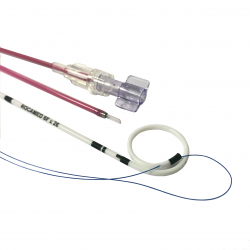

RocaJJ Soft Multilength – Hydro-Coated PolyUrethane Ureteral Stent